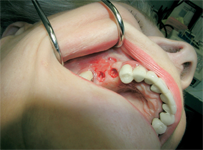

- Otevřený, externí, vnější, laterální sinus lift

Více - Používané přístroje, technologie, materiály

LAS Kit

Souprava pro laterální přístup k sinus liftu, speciálně navržena pro bezpečný a méně invazivní laterální přístup k nadzdvihnutí membrány sinu. LAS Kit nabízí v závislosti na anatomii dutiny ústní a plánech operace různé využití.